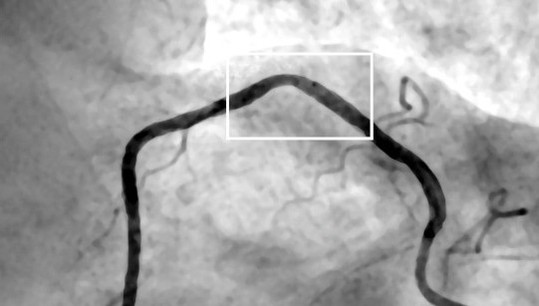

Ангиографическое изображение артерии реального пациента. Прямоугольник — это локальная область со стенозом, которую исследовали ученые. Источник: Иван Бессонов

На первом этапе проекта ученые работают над созданием максимально достоверной модели. При ее составлении они использовали реальные результаты исследования инвазивной коронарной ангиографии пациентов с ишемической болезнью сердца. Таким образом, им удалось смоделировать поток крови в условиях, максимально приближенных к реальной медицинской диагностике.

«На основе данных инвазивной коронарной ангиографии мы разработали трехмерную геометрическую модель участка артерии со стенозом. Используя данные о пульсации давления на входе в исследуемый участок артерии, мы провели гемодинамическое моделирование и получили результаты течения крови для полного кардиоцикла. Эти результаты показали, что за стенозом формируется низкоскоростной вихревой поток, а также возникает область высоковязкой крови, где вязкость увеличивается до двух раз», — поясняет младший научный сотрудник лаборатории многомасштабного математического моделирования УрФУ Илья Стародумов.